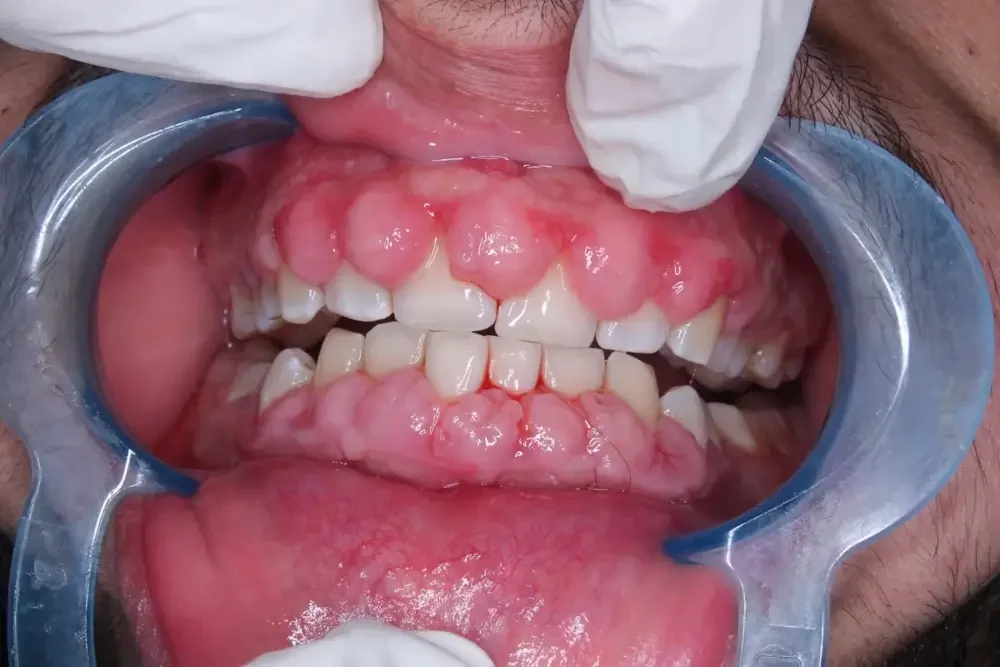

Daging tumbuh di gusi, atau yang sering dikenal dengan istilah hiperplasia gingiva, adalah kondisi di mana terjadi pertumbuhan jaringan gusi yang berlebihan.

Kondisi ini dapat menyebabkan pembengkakan atau tonjolan pada gusi yang terlihat mencolok dan sering disertai rasa sakit atau perdarahan ringan.

Hiperplasia gingiva adalah kondisi di mana jaringan gusi tumbuh secara berlebihan akibat peradangan atau iritasi. Salah satu penyebab paling umum dari kondisi ini adalah kebersihan mulut yang buruk, yang menyebabkan penumpukan plak dan karang gigi.

Plak yang menumpuk di gusi dapat memicu peradangan yang berujung pada pembengkakan jaringan gusi. Selain itu, beberapa obat-obatan, seperti obat antikonvulsan dan obat penghambat saluran kalsium, juga dapat menyebabkan efek samping berupa pertumbuhan gusi yang berlebihan.

Pembengkakan atau Tonjolan pada Garis Gusi

Salah satu tanda pertama yang sering terlihat adalah adanya pembengkakan atau tonjolan pada garis gusi. Pembengkakan ini bisa muncul secara tiba-tiba atau berkembang secara perlahan, dan bisa terasa lunak atau keras saat disentuh.

Jika gusi Anda mengalami perubahan warna, tekstur, atau tampak bengkak, itu bisa menjadi tanda bahwa ada masalah dengan jaringan gusi.

Gusi yang sehat umumnya berwarna merah muda dan memiliki tekstur yang halus. Perubahan yang mencolok, seperti gusi yang menjadi lebih pucat, merah tua, atau bahkan berdarah, harus diwaspadai dan segera diperiksakan.